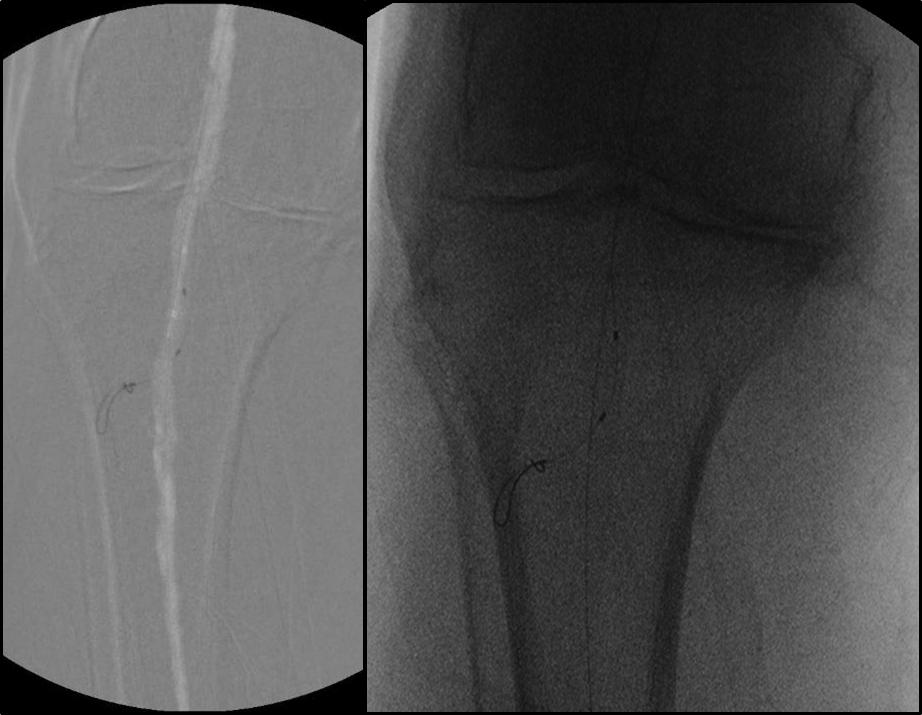

BTK病变多为长段、弥漫、钙化、CTO,多累及踝下(BTA)

各分支 CTO 解剖特点

三大主要分支的CTO近端与远端常见位置:

总体特点:

膝下通常有单个或数个可见的流入道;

病变常为单个或多个CTO组合,总长度可达20cm;

部分患者存在踝上交通动脉或完整的踝下足底弓,为逆向开通提供可能。